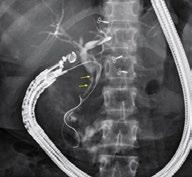

Een belangrijke ontwikkeling in dit vakgebied is het gebruik van lumen-apposerende metalen stents (LAMS). Deze stents zijn speciaal ontworpen om een fistel of verbinding te maken tussen verschillende delen van het maagdarmkanaal, maar via endoscopische weg waardoor het herstel zeer snel verloopt.

Voor patiënten die een gastric bypass-operatie hebben ondergaan en vervolgens een endoscopische retrograde cholangiopancreatografie (ERCP) nodig hebben, kan de LAMS EDGE-procedure worden toegepast om een verbinding te maken naar de uitgesloten maag. Deze techniek wordt gebruikt als de galblaas reeds is verwijderd.

© Hotaxios stent Boston scientific © Hotaxios stent Boston scientific 3. EDGE TECHNIEK: ERCP NA GASTRIC BYPASS

5. CHOLEDOCHODUODENOSTOMIE

In gevallen van een tumor t.h.v de pancreas of galwegen en waarbij een ERCP niet mogelijk is, kan de galweg gedraineerd worden d.m.v. deze techniek.

6. RENDEZ-VOUS TECHNIEK

Wanneer een traditionele ERCP faalt, kan de EUSgeleide rendez-vous-techniek worden toegepast. Door middel van EUS wordt de galweg aangeprikt

en wordt een draad antegraad opgevoerd tot voorbij de papil van Vater. Deze wordt dan opgepikt en daarna wordt een klassieke ERCP uitgevoerd.